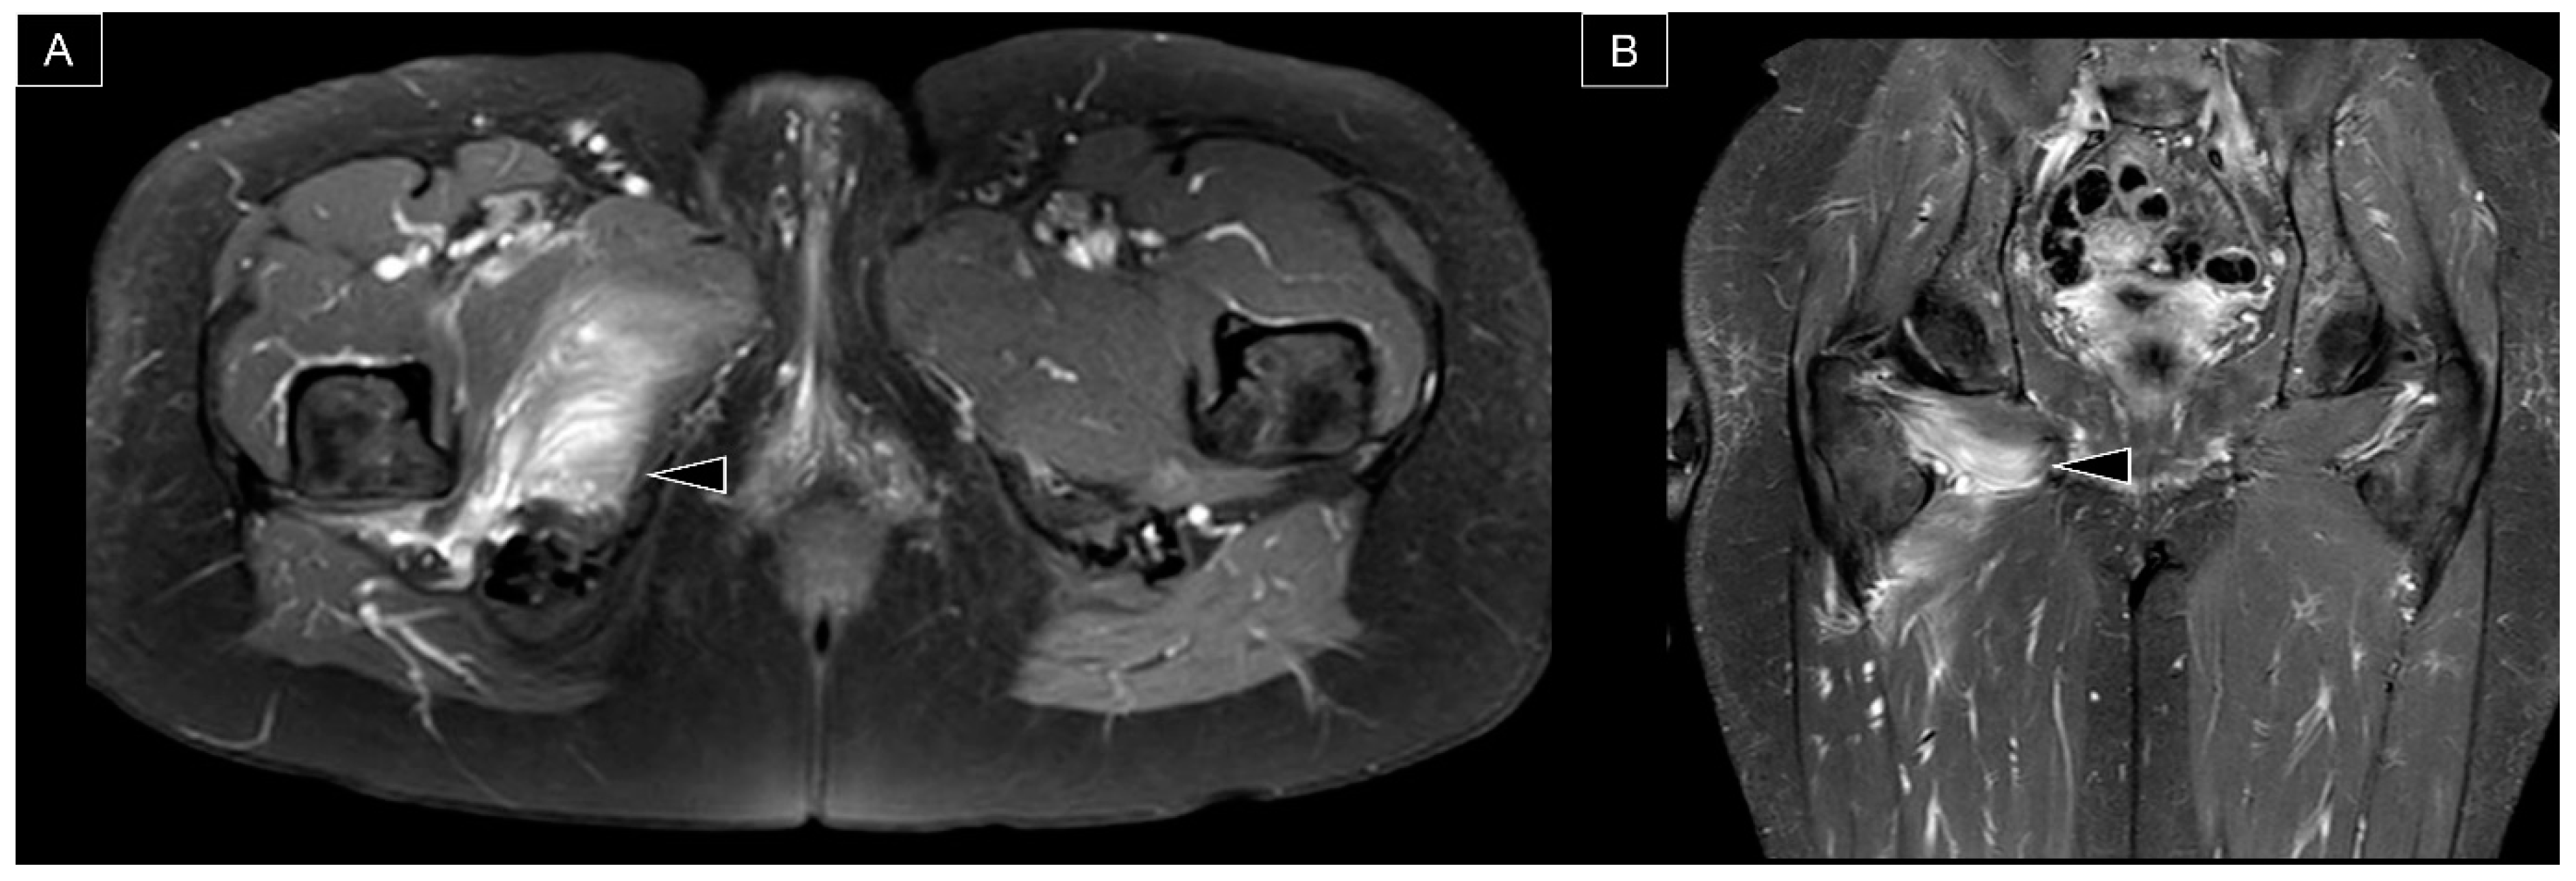

7. MRI Assessment